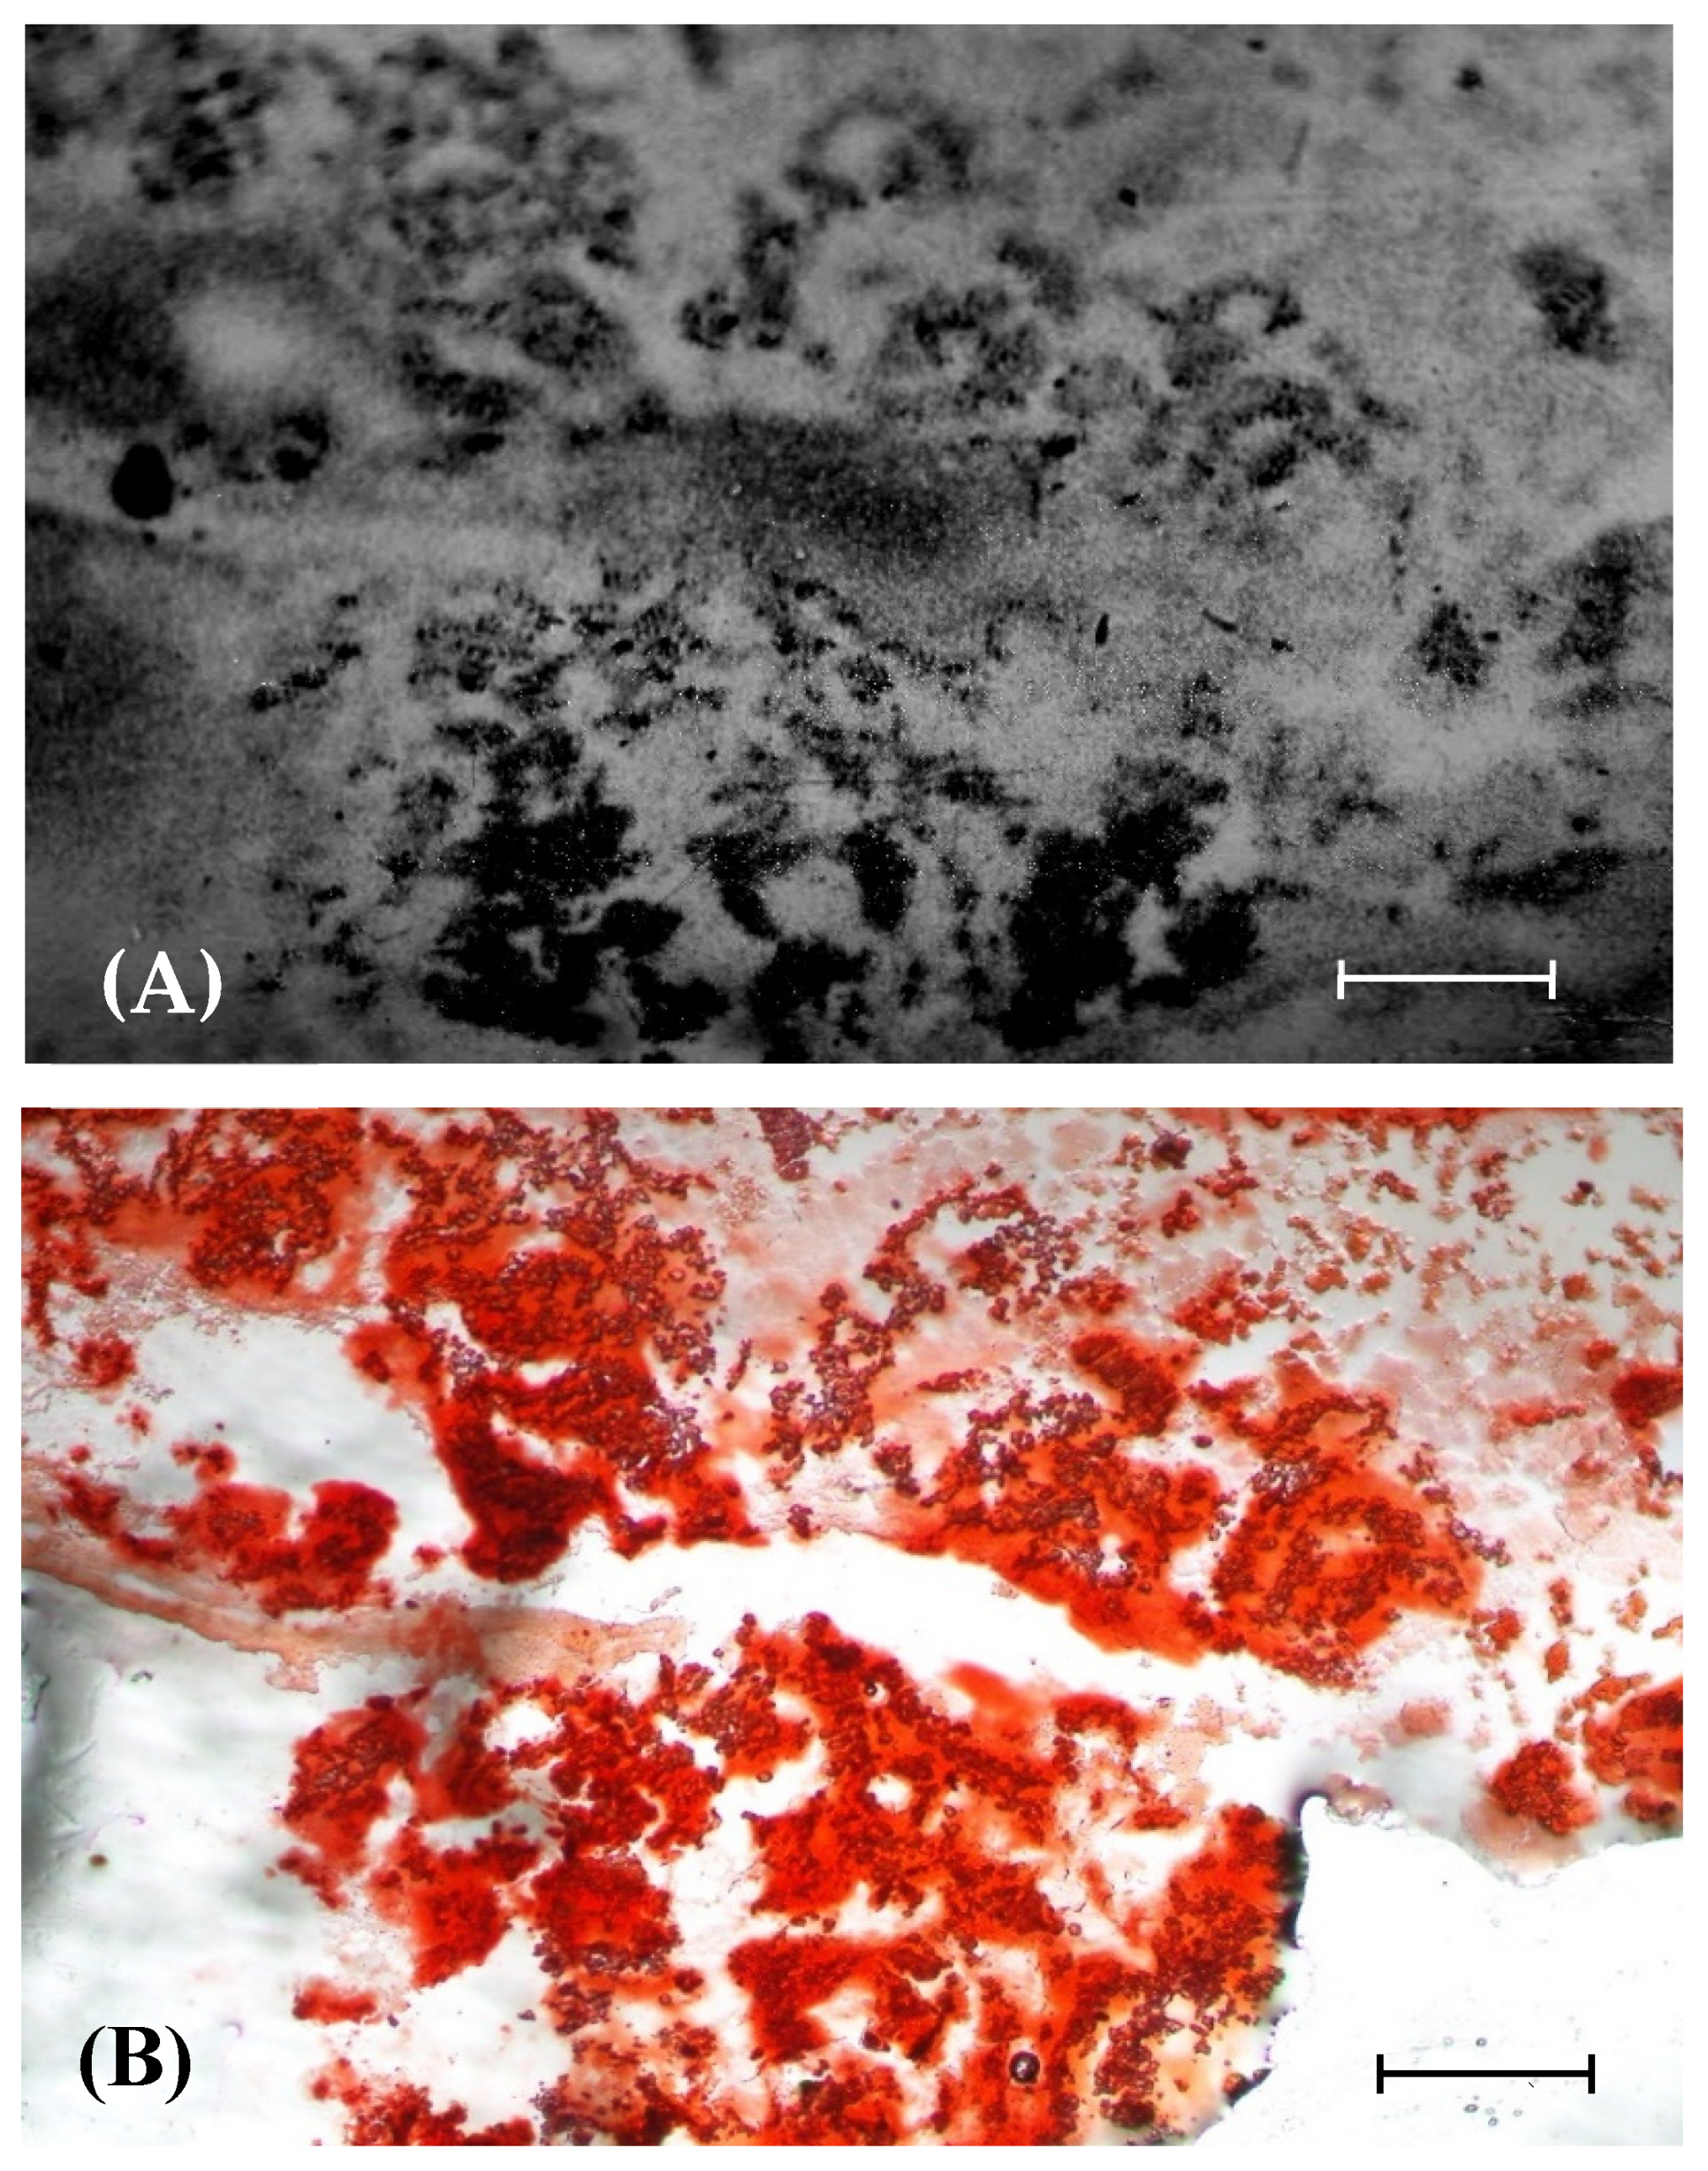

3.5. Relationship between BA Retention and Calcification in OS Tissue